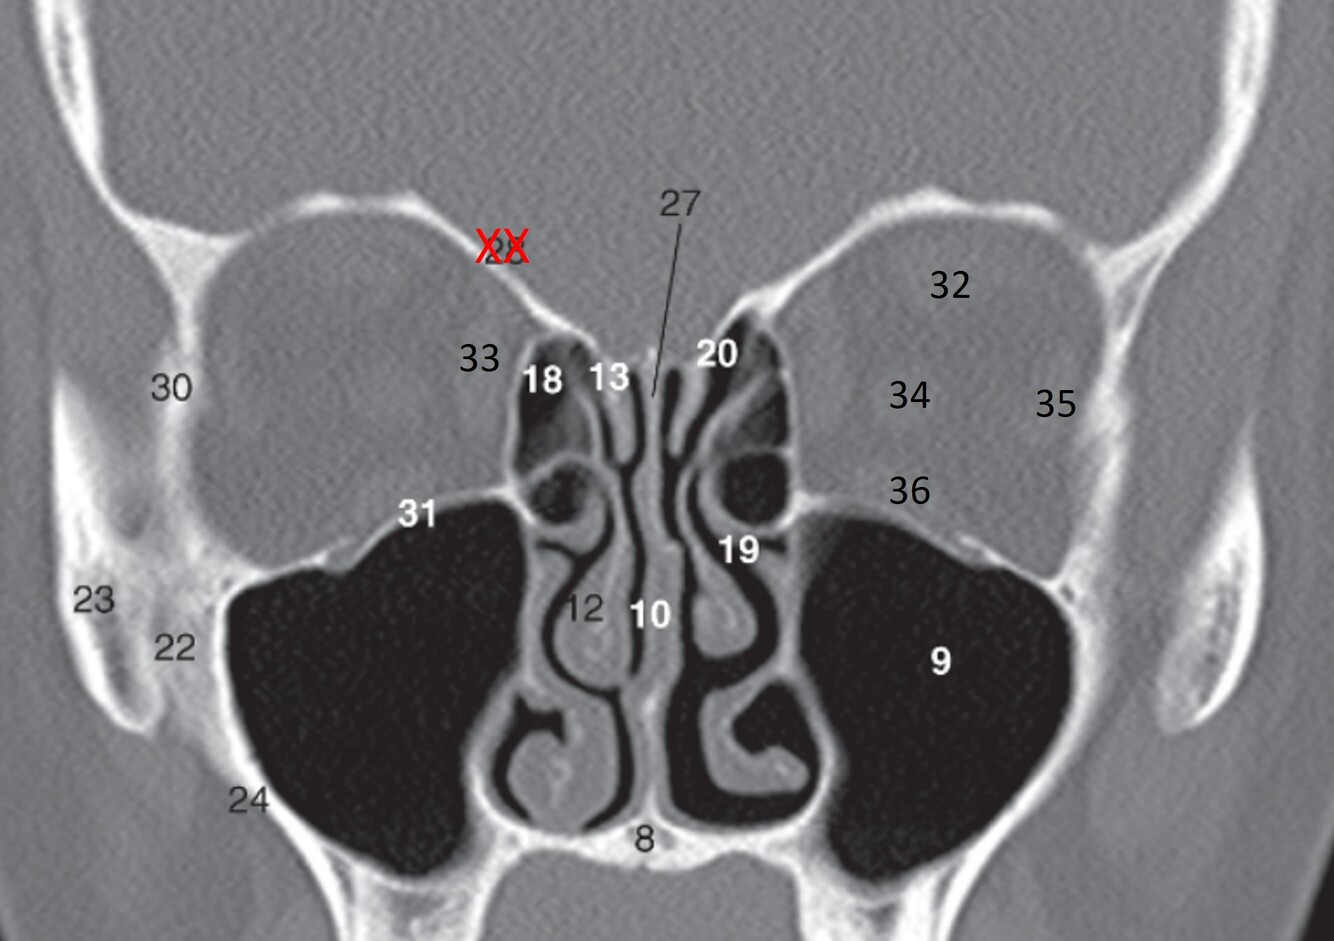

10

Label 20,22,23,24,27,30,31

A

20-Lt. Superior nasal meatus

22=Rt maxilla (zygomatic process)

23=Rt zygoma

24=Lateral wall of Rt maxillary sinus

27=Perpendicular plate (ethmoid)

30=Rt. Lateral orbital wall (zygoma)

31=Rt. Orbital floor (maxilla)

11

Label 32-36

32=Lt superior rectus muscle

33=Rt medial rectus muscle

34-Lt Optic nerve

35=Lt lateral rectus muscle

36=Lt inferior rectus muscle